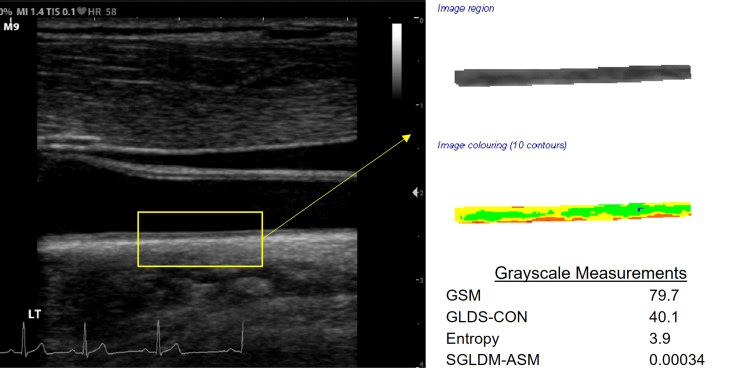

Below is a B-mode ultrasound image of the distal common carotid artery with far wall extraction, color coding of normalized and standardized grayscale values, and grayscale measurements of early arterial injury.